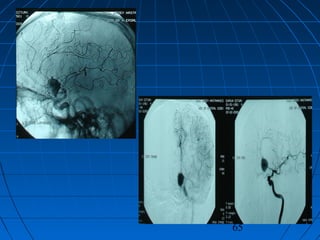

 DÖ: 59 yaşında erkek hastaDÖ: 59 yaşında erkek hasta

 GKS 14 (WFNS grade 2)GKS 14 (WFNS grade 2)

 Fisher grade IVFisher grade IV

64

CERRAHİCERRAHİ

 Sol pterional trans-sylvian yaklaşımSol pterional trans-sylvian yaklaşım

 AcomA Anevrizması kliplendiAcomA Anevrizması kliplendi